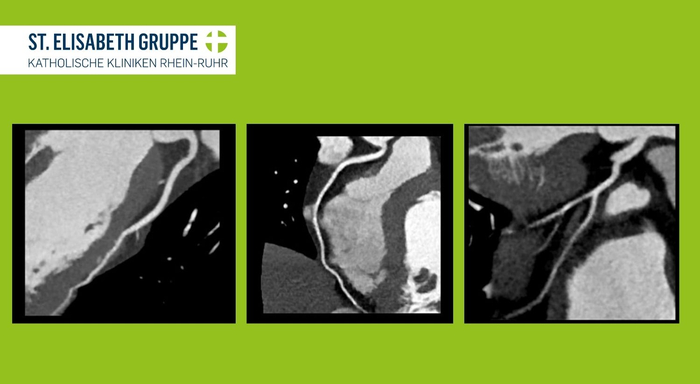

Die CT der Herzkranzgefäße (CT-Koronarangiographie oder Herz-CT) ist ein wichtiges bildgebendes Diagnoseverfahren und bietet eine nicht-invasive Möglichkeit, die Herzkranzgefäße zu untersuchen und die der Notwendigkeit einer Herzkatheteruntersuchung zu beurteilen. Mit dem sogenannten Calcium-Scoring kann das Ausmaß der Verkalkungen der Koronargefäße (Gesamtplaquelast) sehr genau untersucht werden. Hieraus können bereits entscheidende Hinweise für das Risiko für Herzerkrankungen (z. B. Herzinfarkt) abgeleitet und die Therapie dementsprechend angepasst werden. Darüber hinaus ist die Herz-CT in der Lage, sogenannte „weiche Plaques“, also nicht verkalkte Ablagerungen an den Wänden der Herzkranzgefäße darzustellen, wodurch eine koronare Herzerkrankung (KHK) früher diagnostiziert und therapiert werden kann. Fehlen Verkalkungen und weiche Plaques, lässt sich eine koronare Herzerkrankung durch die Herz-CT nahezu ausschließen. Dadurch wird dem Patienten eine invasive Herzkatheteruntersuchung erspart.

Herz-CT

Mit einer Herz-CT können zum Beispiel Verkalkungen festgestellt werden